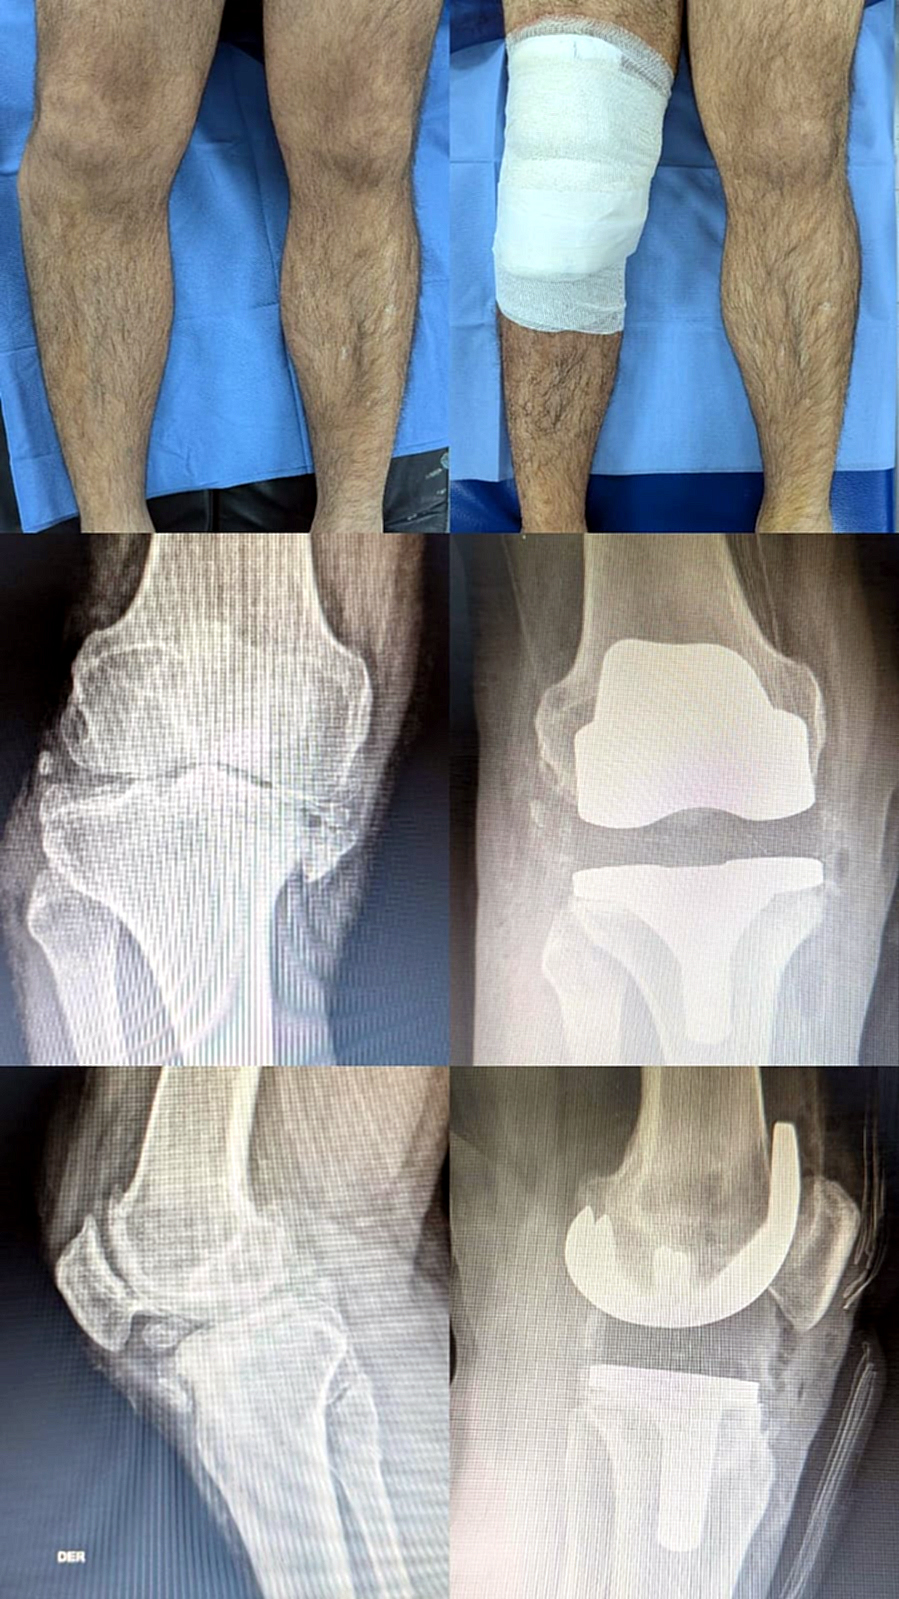

Las lesiones de ligamentos y meniscos son las más frecuentes en pacientes menores de 40 años, mientras que en los adultos mayores, la causa principal de cirugía es la artrosis y la colocación de prótesis de rodilla.

¿Cómo disminuir el dolor por artrosis (gonartrosis)?

Factores que influyen en la aparición de artrosis de rodilla: